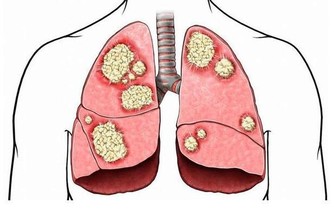

當咳嗽遲遲不癒的時候,就會轉成虛寒型咳嗽,中醫有“久咳必虛”的說法,若咳嗽遲遲沒有改善的話,往往導致正氣虛弱,內在陽氣不足,這樣的話更不能生吃梨,不過可以選擇川貝煮梨來改善症狀。川貝是一味中藥,入肺、心經,有化痰止咳,清熱散結的作用。川貝與雪梨、冰糖並用,則起化痰止咳,潤肺養陰功效。治療久咳不愈,痰多,咽乾,氣短乏力等。